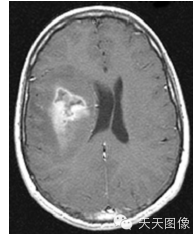

下面只上几张比较中规中矩的肿瘤图像。

上面是一些典型的脑肿瘤图,图中的白块就是肿瘤。为了让大家看的更直观,特地选出来一些比较好分割的图像,但是也并不是什么方法都能分割出来的,就我个人知识而言,不进行任何预处理,没有一种方法可以自动地直接将这些肿瘤都给分割出来。不信可以去问问周边搞图像的人,如果有,请务必告诉我。

下面是我的分割结果,算不上完全自动,但是也是基本上不需要监督。(仔细看肿瘤周围叠加的轮廓,就是分割的结果)

用到的方法就是水平集。